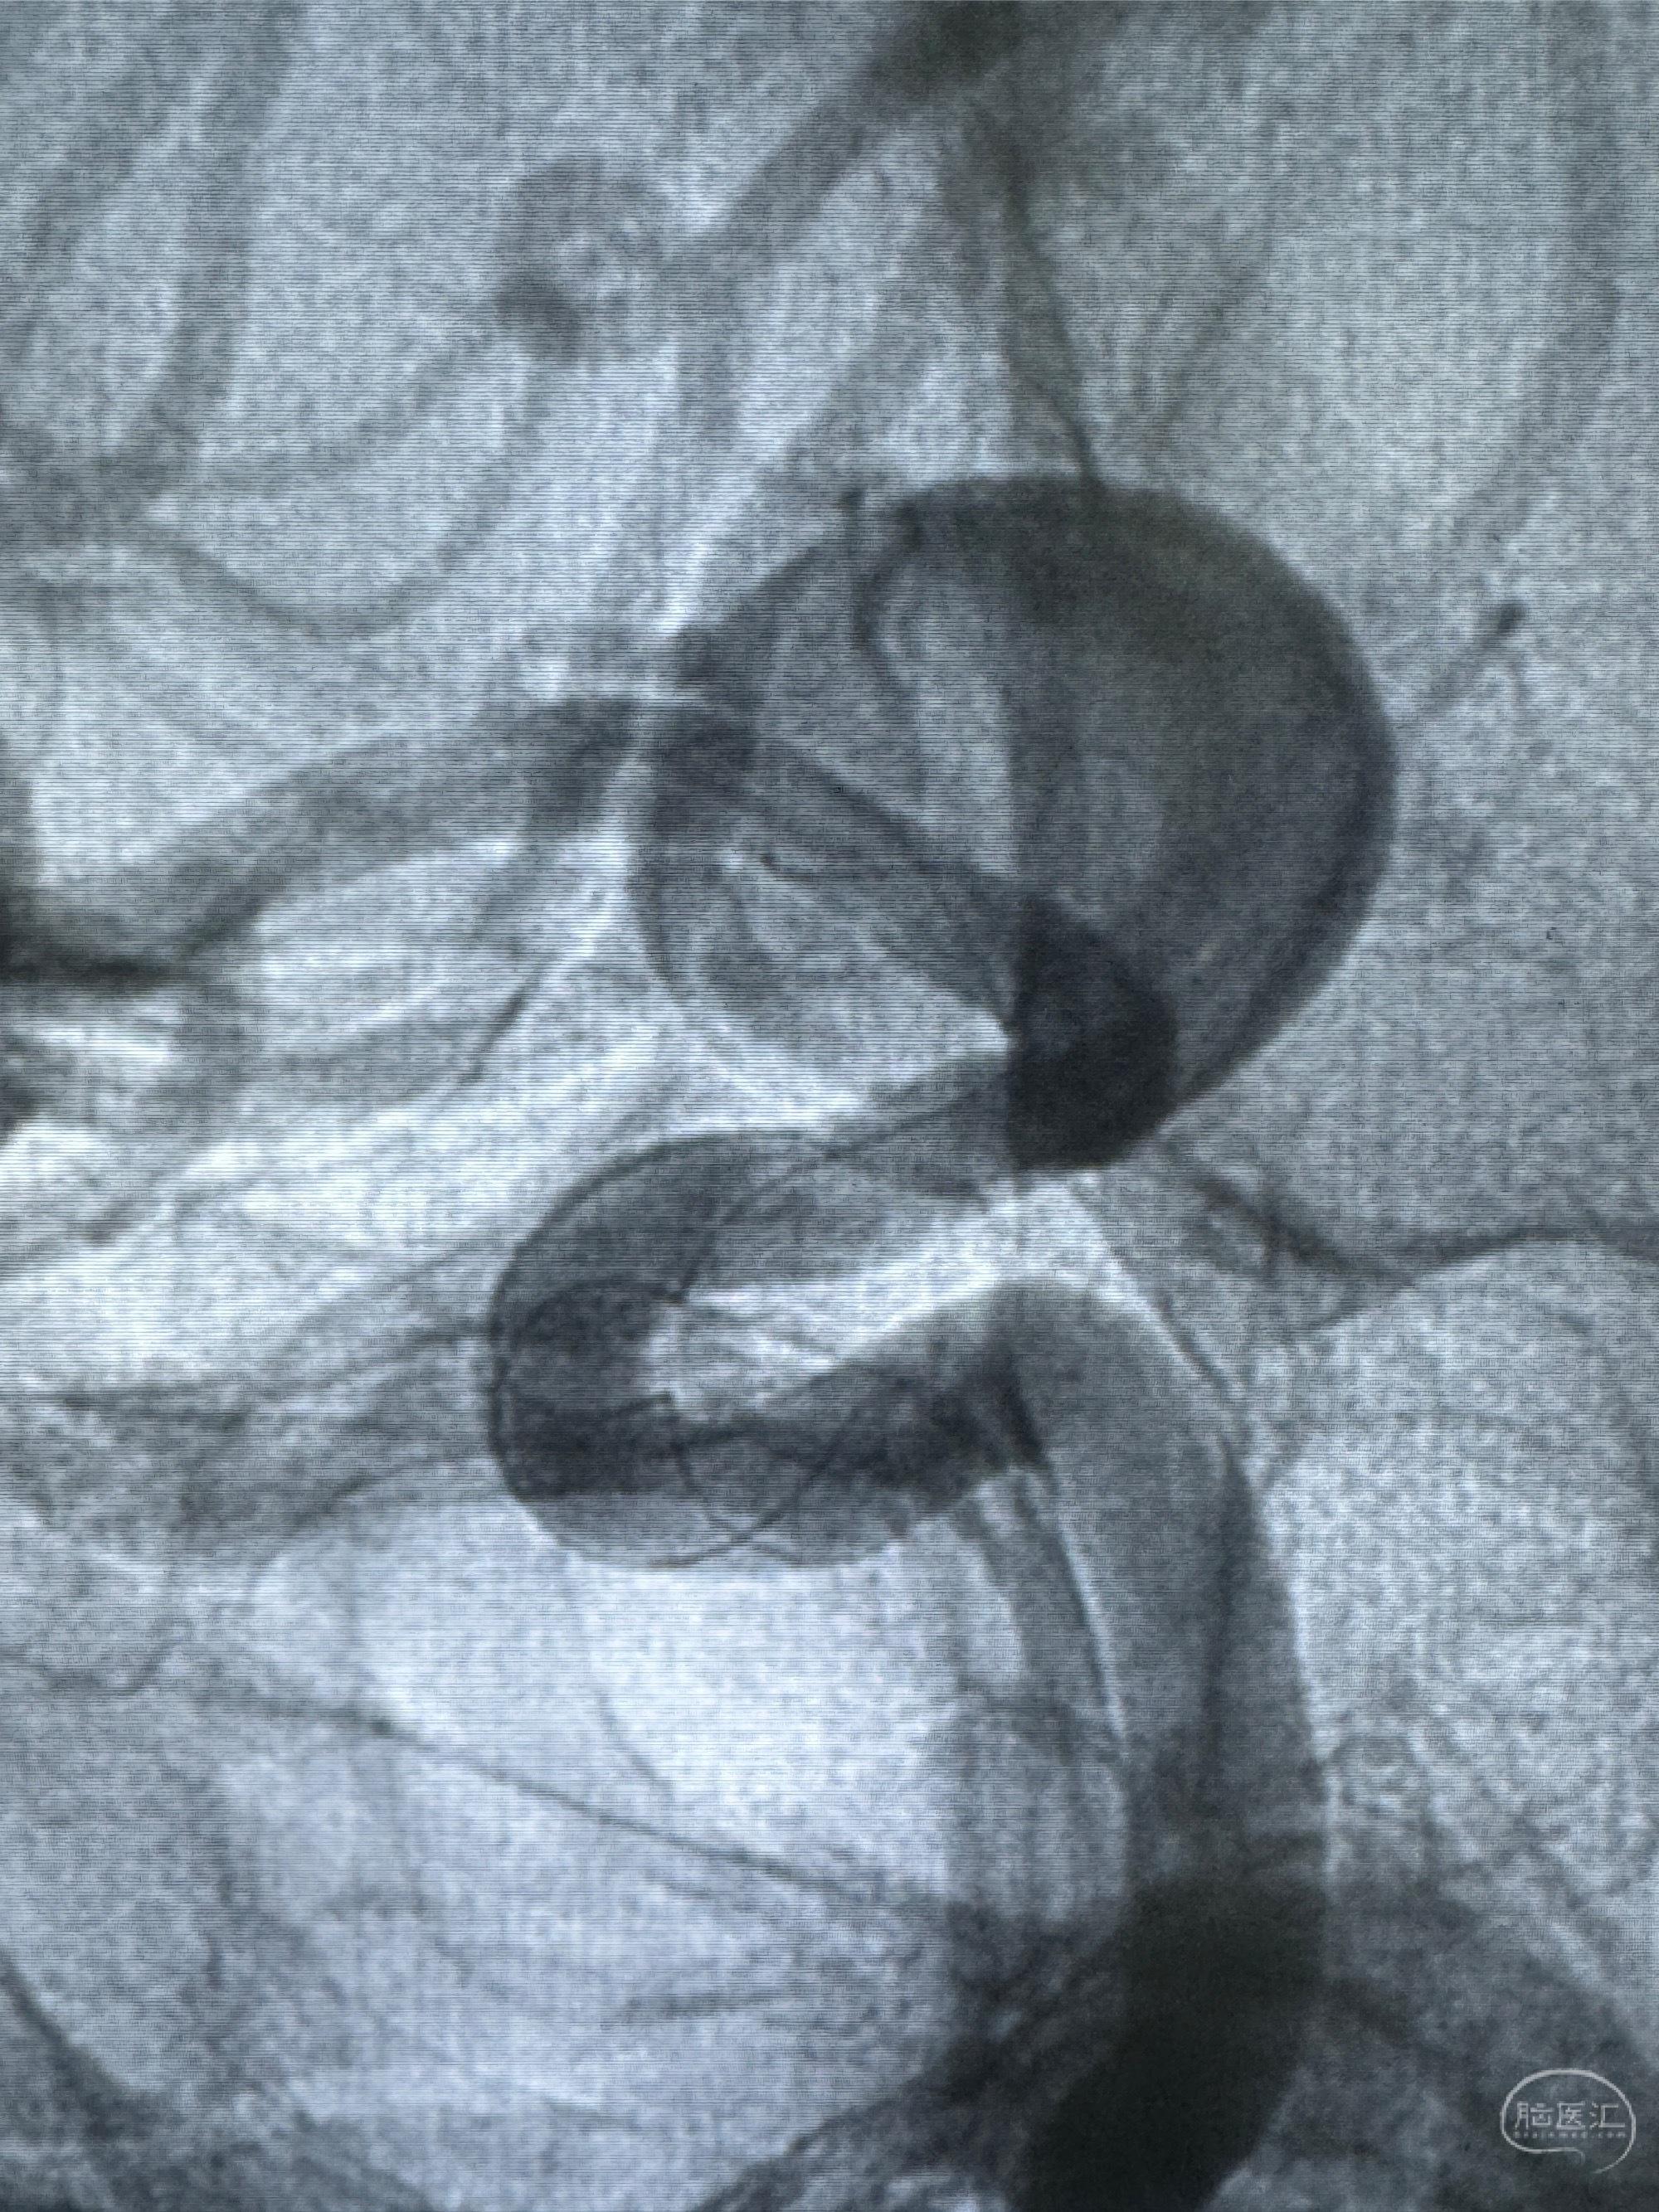

测量动脉瘤的大小:16*13.8*7.6mm大小,较原先变大,考虑双抗后瘤内血栓溶解可能

4.5-30mmTurbridge密网支架,于M1近心端打开

透视下支架释放满意

多角度显示支架打开情况

造影显示支架贴壁情况